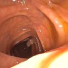

| (a) | (b) | (c) | (d) |

In this paper, we present a deep learning model for realtime visualization of missed colon surfaces directly on the colonoscopy video frames without doing any prior offline 3D reconstruction using contiguous sets of frames. Specifically, we make use of prior 3D reconstructed virtual colonoscopy (VC) [7, 8] data, created from a computed tomography (CT) scan, to produce training data for missing surface visualization (Figure 1b–d). This is used in conjunction with OC data for the same patient to drive an unpaired image-to-image translation with a modified lossy CycleGAN [4] and a new enforced shared OC and VC latent space representation. The lossy CycleGAN [4] by itself overfits due to the sparse training data for the missing surface task (most OC frames have no or few missing surface green pixels as opposed to the dense depth maps for which the lossy CycleGAN was originally proposed) and can easily hallucinate structures which do not exist, as shown in Figure 1. Adding a shared latent space forces the network to preserve structures (and avoid hallucination) when translating between domains. With added Gaussian noise, we also show that the same framework with shared latent space representations can be used to generate realistic one-to-many mappings from VC to OC and OC to OC for augmenting OC datasets in computer-aided detection and classification pipelines.

In order to create training data for per-frame missing surface visualization, the opacity of the 3D colon mesh is lowered such that the more opaque regions indicate the missed surfaces, which are colored green in Figure 1c. The per-frame missing surface data is generated through Blender and example videos are provided111Supplementary Video: https://youtu.be/x1-wwCiYeC0. Figure 1 shows a typical colon anatomy along with the haustral folds and the pictorial representation of a missed surface for a certain endoscope camera position. To aid the model with the image-to-image domain translation task, we added the missing surface information in green channel on top of the VC rendering of the colon (Figure 1d).